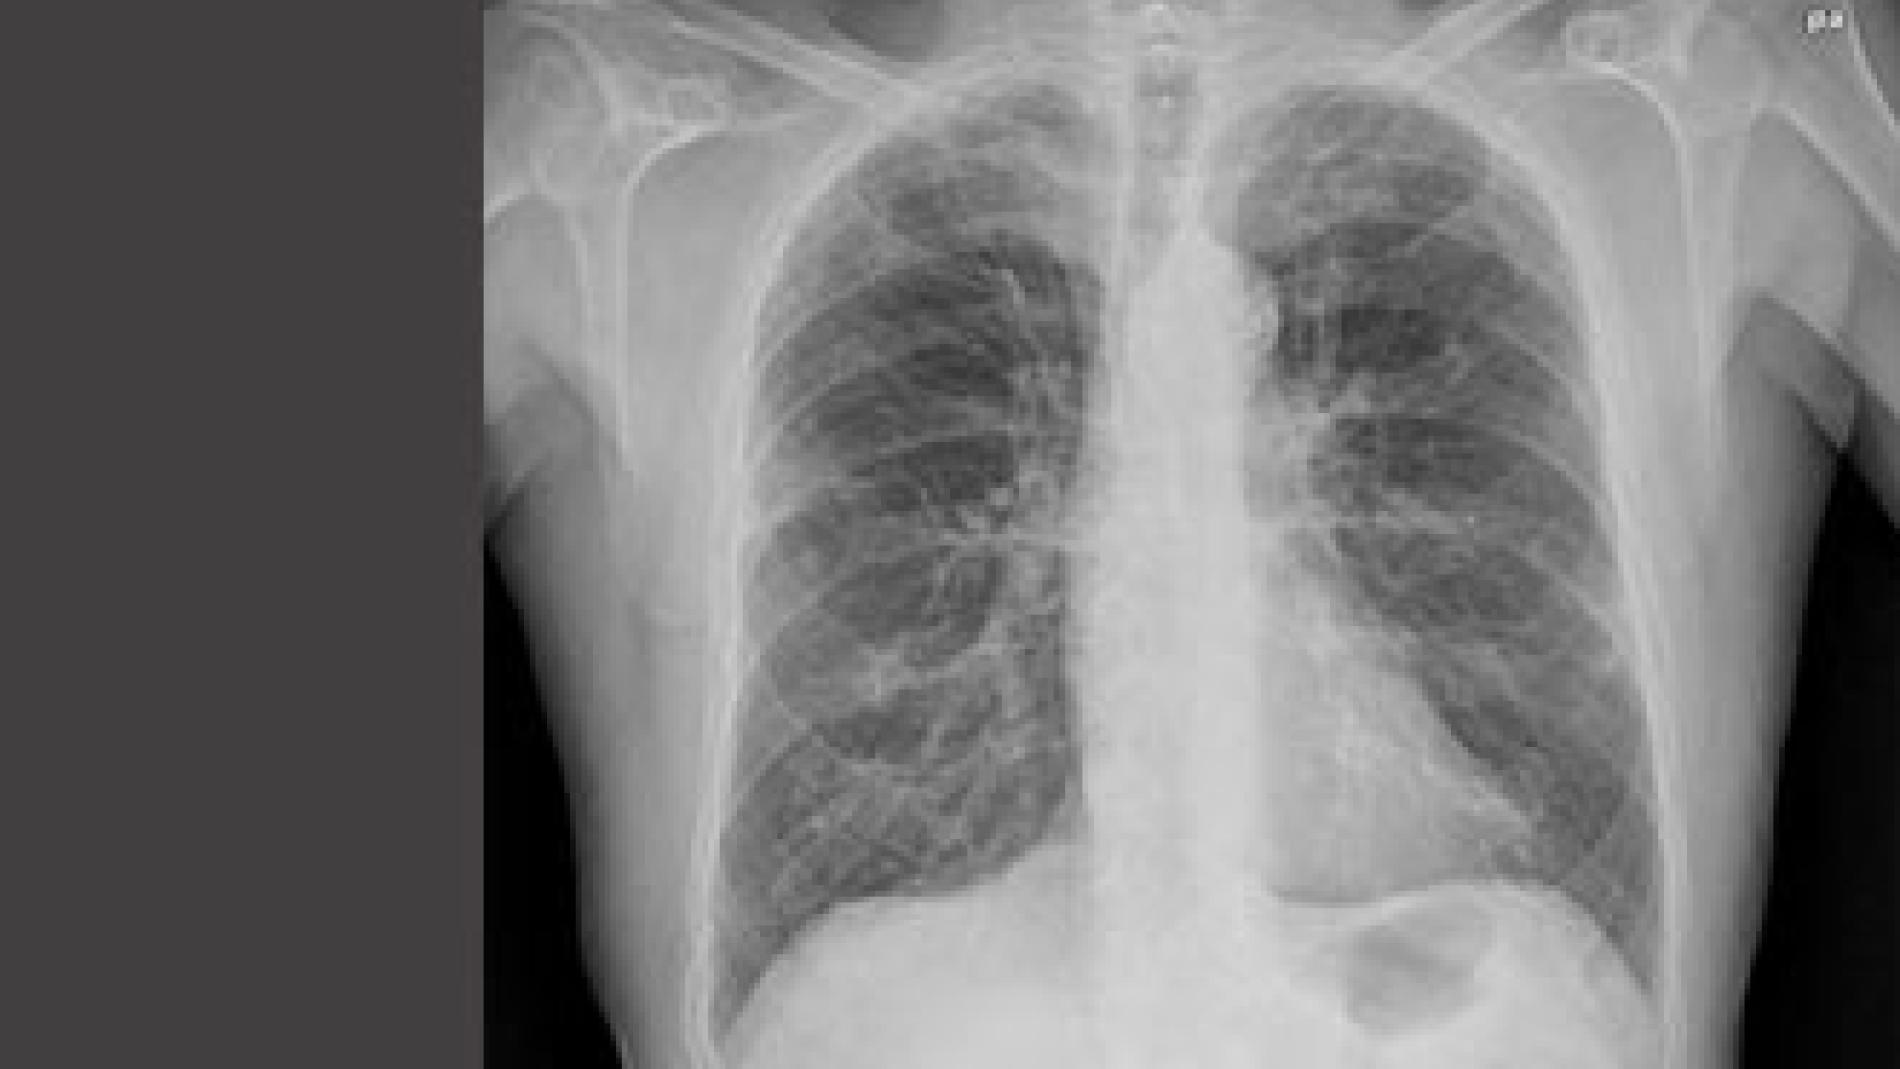

A recent multicenter study, in which participates Vall d'Hebron Institut de Recerca (VHIR) and funded TV3 La Marató, assessed the impact of Chronic Obstructive Pulmonary Disease (COPD) in mortality, length of hospital admissions and ICU complications in those who suffer it. The results of this research, where CIBER researchers of Respiratory Diseases (CIBERER) from Hospital del Mar, Joan XXIII Hospital and Hospital Negrin also collaboreted, leave no doubt about the negative effects of snuff: patients with COPD need an average of 14 ventilator days, 24 days in the ICU and 42 days in hospital as a whole. Scientific evidence of these clinical data results in the costs of COPD to the healthcare system and the impact they might have on improving health habits of the people smoking, as well as improved health, hope and quality of life of these patients.The UCI study, published in the latest issue of the journal CHEST, included critically ill patients exposed to mechanical ventilation (breathing machine) with no evidence of respiratory infections and patients with COPD not exacerbated, meaning they are not admitted because of this disease or from complications of COPD itself. The results show that intubated patients with COPD exacerbated are not exposed to a higher risk of ventilation-associated pneumonia, but have higher mortality than other patients admitted to the Intensive Care Unit (ICU).